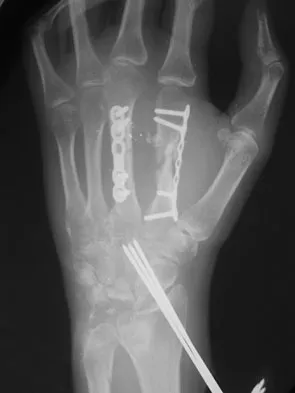

Figure 19 shows the radiograph of a 12-year-old boy who sustained an injury to his hand when another child fell on him. Management should consist of

Explanation